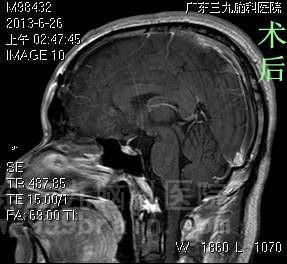

原来,阿兵一个月前无明显诱因开始出现头痛,伴有视力下降,一周前症状较前加重,当地医院就诊,行头颅CT检查提示三脑室占位。经我院头颅MR检查提示鞍上区垂体后上缘示一类椭圆形占位病变,大小约27.2*20.6*19.5mm,垂体柄受压稍前移,垂体受压,矢状位示邻近视交叉受压前移。原来失准的三分球的罪魁祸首是脑瘤。

完善相关检查后,由综合神经外科鲁明主任主刀,在全麻下行经额纵裂入路三脑室占位切除术,术中显微镜下见肿瘤位于三脑室,呈白色、血供不丰富、边界清、质软,予肿瘤镜下全切,术中对垂体、垂体柄、视神经保护完好,手术顺利结束。术后阿兵送入专科监护病室,经专科治疗护理,未出现尿崩、离子紊乱等术后并发症,视力明显较术前好转,康复出院。术后病理结果:粘液囊肿。